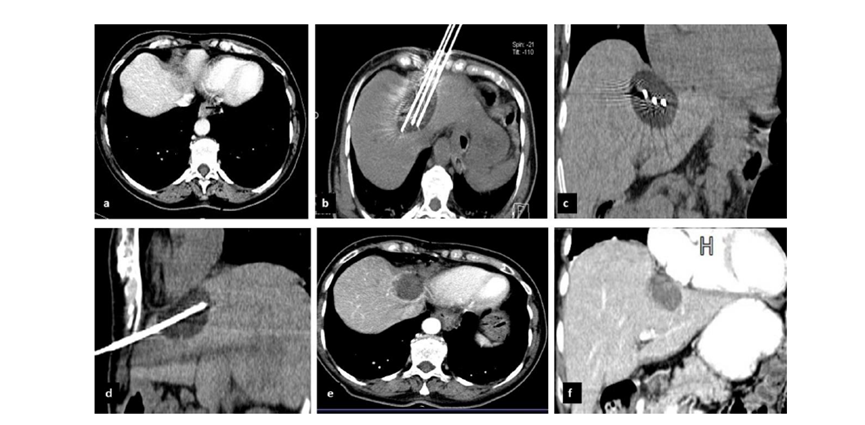

79 岁男性,肝转移(结直肠癌)肿瘤的完全消融病例

( a ) 轴向 MRI 和 ( b ) 轴向 CT 显示肝S8段有一个16mm的病灶,邻近肝缘。( c )冷冻消融期间CT显示放置了2个冷冻探针,低密度冰球包围病灶。(d)术后1个月随访 CT显示冰球对应的坏死区域,未见复发。(f)与基线影像(g)相比,12个月后的FDG-PET/CT显示未见FDG摄取。

(a)轴向CT显示病变位置毗邻心脏和上腔静脉(黑色箭头)。1个月后的轴向(e)和冠状位(f)增强CT扫描显示低密度区域,由于肉芽组织反应引起的边缘增强。